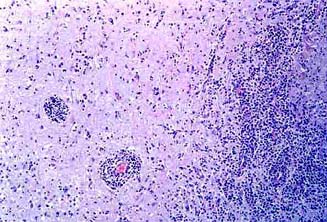

ESTREPTOCOCIA:

Meningoencefalitis purulenta.